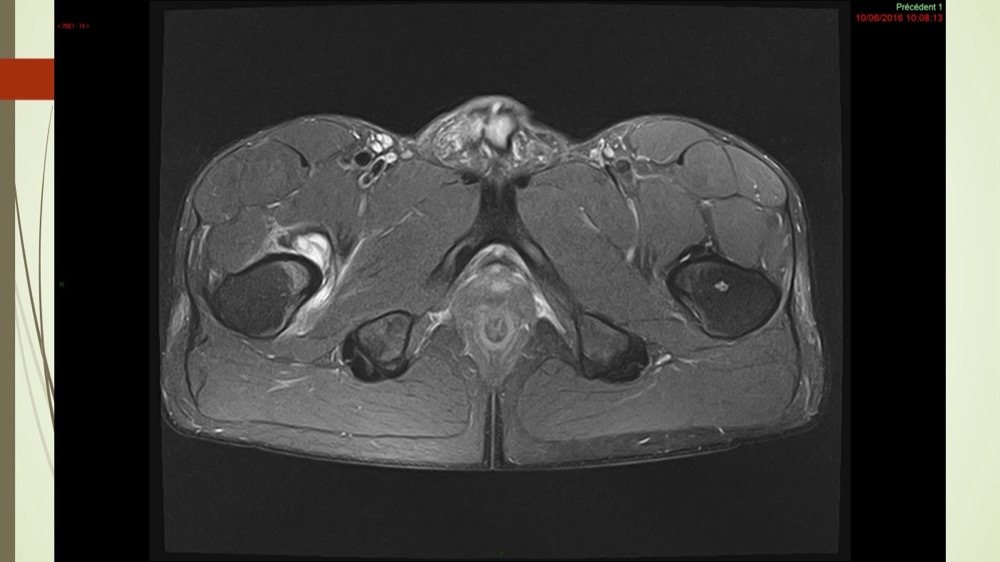

Coxalgie traînante

Kévin Mahé 29/06/2022